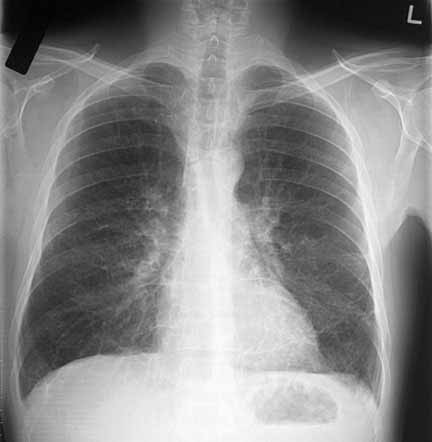

Apakah bronkhitis bisa diobati? Tentu saja bisa. Rontgen dada adalah bagian dari diagnosis penyakit bronkhitis. Kemudian, penderita akan diberi beberapa macam obat seperti aspirin atau asetaminofen, antibiotik, trimetoprim-sulfametoksazol, tetracyclin atau ampisilin. Selain pengobatan medis, alternatif pengobatan menggunakan obat herbal dari ramuan alami juga bisa dilakukan untuk menyembuhkan bronkhitis.